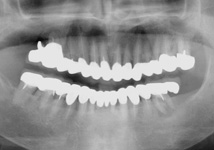

カリエスが多く、歯周病が進行し、硬いものが噛みにくいと、当院を受診され、歯周再生治療と、審美補綴治療によってトータルコーディネートをしました。今は、歯周病も改善し、痛みもなく、よく噛めると喜んでいただいております。